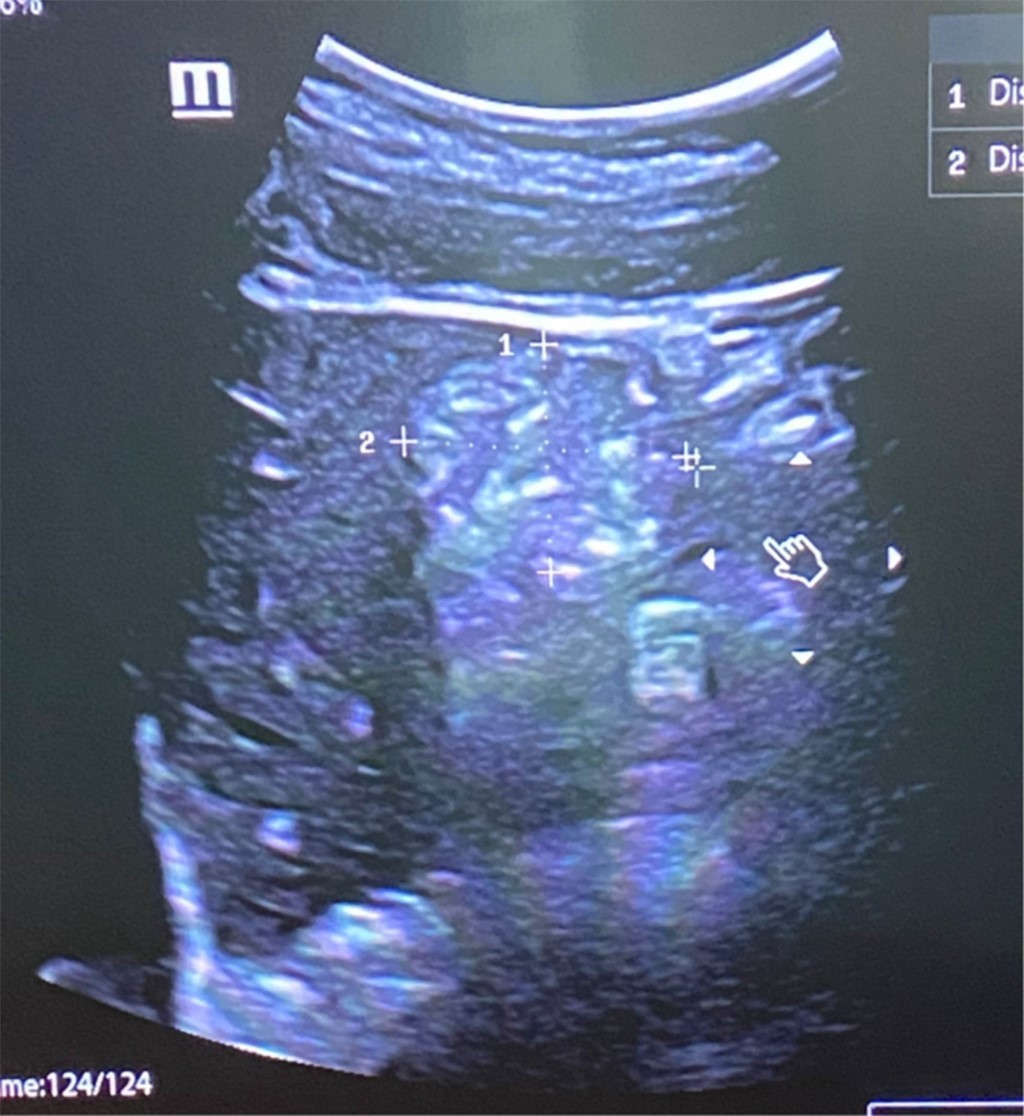

Se presenta el caso de una mujer de 41 años que acude programada para realización de panendoscopia secundario a enfermedad ácido péptica de dos años de evolución. Dentro de sus antecedentes reporta consumo de cuatro cigarrillos al día, alcohol a razón de tres bebidas estándar por semana, como antecedentes quirúrgicos refiere una cesárea y apendicectomía. Destaca reciente inicio de semaglutida (Ozempic) dos meses previos a su procedimiento para control de peso en dosis de escalamiento, última aplicación dos días antes de su procedimiento. Niega otras enfermedades crónicas-degenerativas y uso de medicamentos. En su valoración preanestésica, la paciente menciona ayuno de 12 horas, presencia de epigastralgia y náuseas leves, índice de masa corporal de 30.48 kg/m2 al momento de su valoración. Se realiza rastreo ultrasonográfico de cámara gástrica encontrando estómago de riesgo (Figura 1), por lo que se decidió la suspensión del procedimiento.

Figura 1